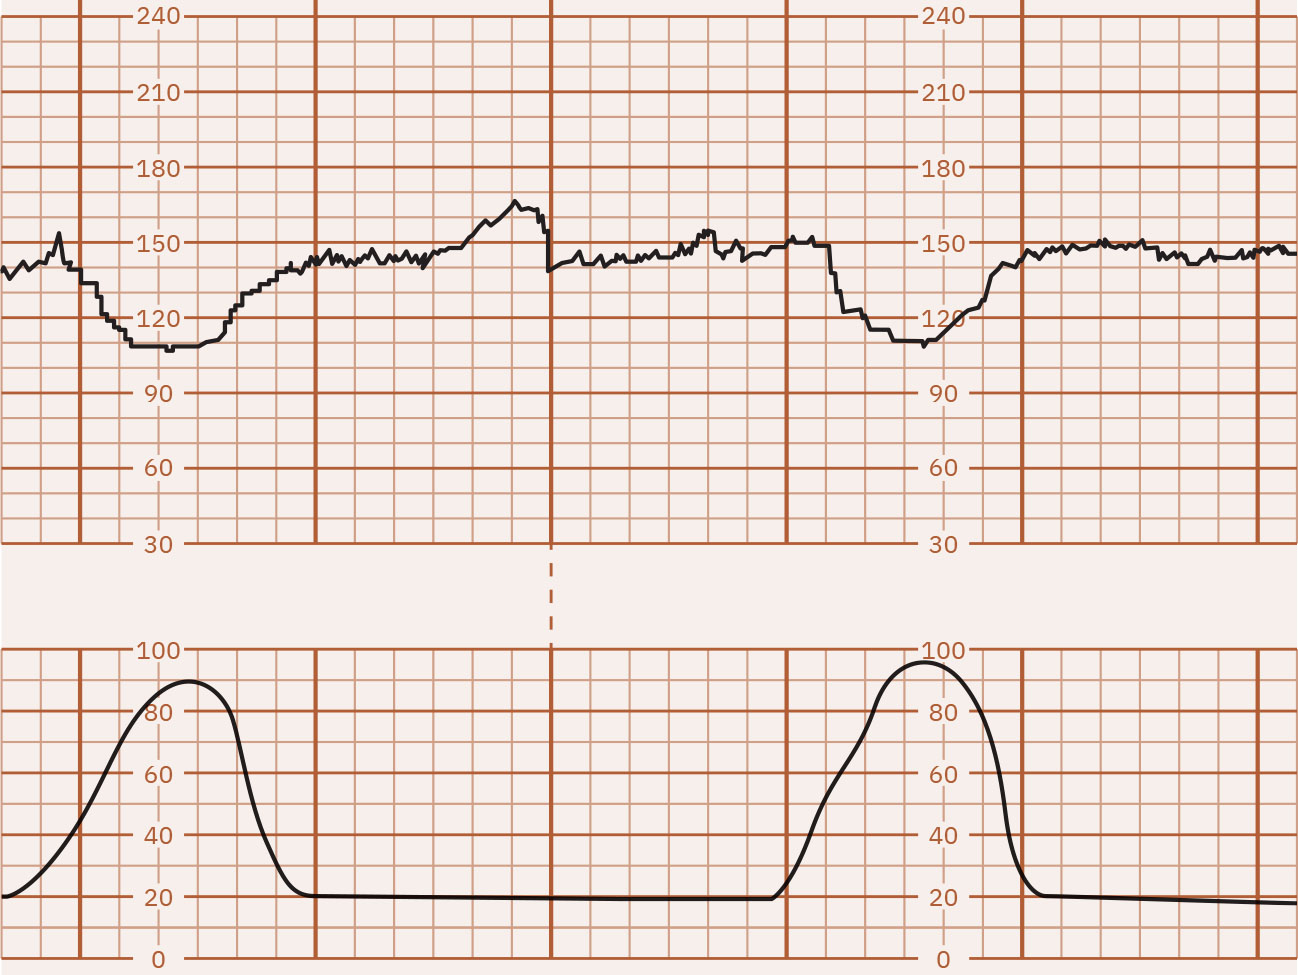

• 기저선: 주요 주기성 변화와 현저한 변이도를 제외한 10분 평균 FHR로, 보통 5-bpm 간격으로 기록합니다. 빈맥은 10분 이상 160 bpm 초과, 서맥은 10분 이상 110 bpm 미만입니다.

약 180 bpm 기저선 빈맥을 보여주는 FHR 추적 예시 Illustration reference: OpenStax Maternal-Newborn Nursing Ch.16.1.

• 기저선을 확인하고 빈맥(10분 이상 >160) 또는 서맥(10분 이상 <110)을 식별합니다.

• 기저선 빈맥에서는 모체(감염/발열, 불안, 탈수, 니코틴, 일부 약물, 갑상선 맥락)와 태아(저산소증, 감염, 빈혈, 미숙성, 부정맥) 기여 요인을 검토합니다.

• 기저선 서맥에서는 모체(저혈압/마취 영향, 대사 원인, 일부 약물, 주요 산과 응급, 모체 맥박 오독 가능)와 태아(아두/제대 압박, 저산소증, 선천 전도 이상) 기여 요인을 검토합니다.